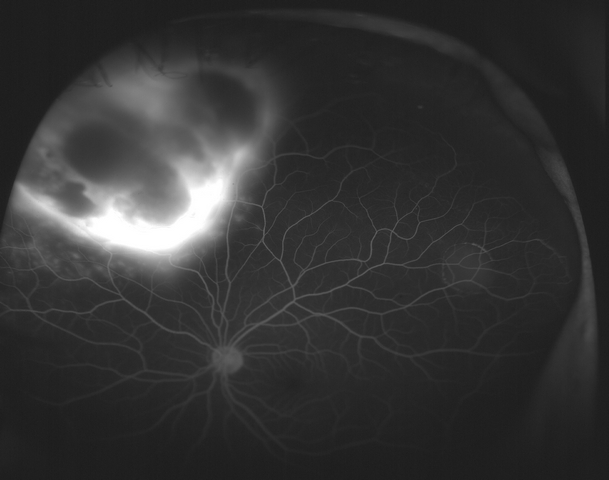

Optos fundus photographs and fluorescein angiogram were performed. The angiogram showed early blockage with some mottled hyperfluorescence that increases in the later phase, with diffuse late leakage overlying the tumor.